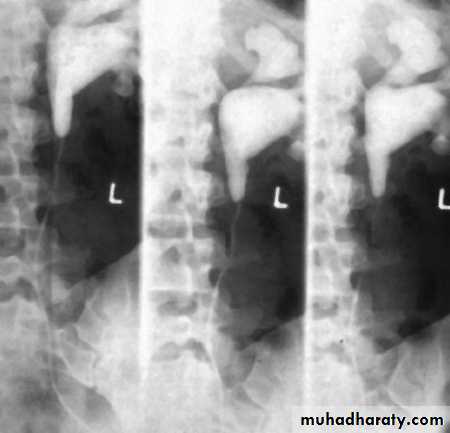

Horse shoe kidney -Kidneys may fail to separate.

-Almost invariably the lower poles remain fused.

-The kidneys axes are more parallel to the spine and malrotated.

-Diagnosis can be made by plain x-ray in some cases.

-US, CT scan and MRI can better demonstrate the anatomy and morphology hence the diagnosis.

-May be an incidental finding.

-PUJ obstruction and calculi formation are common .

IVU shows

1. The kidneys at low position .

2.Close to the spine with long axis parallel to the spine .

3. Malrotation manifested by medially directed calyces.

4- The renal pelvis and ureters are anterior and lateral in position .